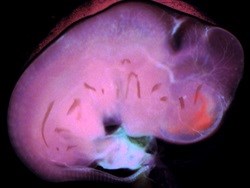

Researchers in the lab of Angelique Bordey, professor of neurosurgery and of physiology, studied exosome nanovesicles found in the cerebrospinal fluid of the developing brains of mouse embryos, stained pink in the accompanying photo. Until the last few years, scientists had believed that the primary job of these nanovesicles was to sweep up byproducts of cellular activity. However, the researchers discovered these nanovesicles contained hundreds of proteins and bits of small RNAs that regulate a key molecular pathway controlling the density of neurons in developing brain. Bordey said it may be possible one day to analyze the contents of these nanovesicles to diagnose neurological conditions such as autism before birth.

To learn more, read the study published online 18 February 2014 in the journal PLOS ONE.